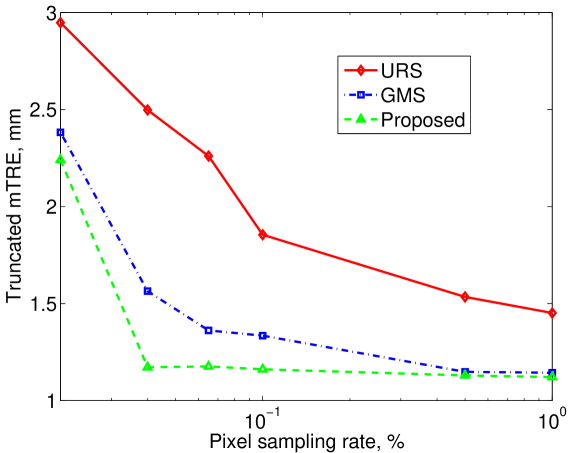

Figure 3 shows the trimmed mean target registration error (mTRE). We compute the trimmed mTRE as the mTRE of the successful (non-failed) cases. The mTRE is minimal for the proposed approach compared to other methods. The proposed approach retains high level of accuracy and robustness even with low pixel sampling rates. This allows to significantly reduce computational time in a practical system without exploding the failure rate or reducing accuracy.

Such results support our conjecture that balancing image exploration induced by URS and the exploitation of the prominent image features induced by GMS using a small problem specific training dataset can significantly improve and accelerate the performance of the registration algorithm. Overall, the proposed technique at 0.1% pixel sampling rate is better than other techniques at 1% pixel sampling rate, simultaneously maintaining zero failure rate and mm accuracy. Thus on average our approach can use 10 times less pixels for registration, achieve 0 failure rate and improve accuracy over the other two techniques. This is significant improvement over both alternative methods and it allows to reduce the time from 210 seconds per registration for pixel sampling rate to 32 seconds per registration for pixel sampling rate in our implementation.